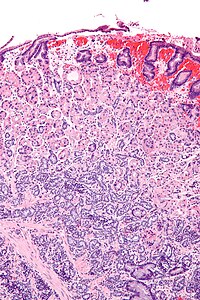

Gastric neuroendocrine tumour - intermed mag.jpg

Micrograph of a neuroendocrine tumour of the stomach. H&E stain.